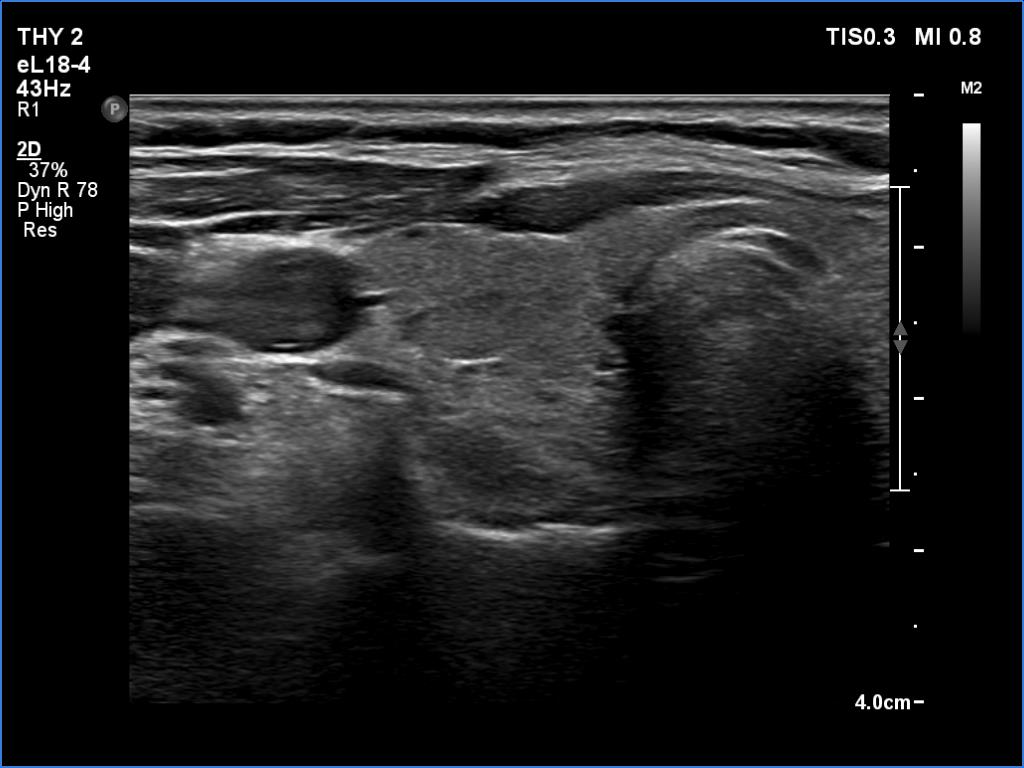

Ultrasonography. The thyroid was echonormal. There were several hypoechoic areas in the right lobe. The left lobe had a large minimally hypoechoic nodule with several tiny cystic areas. The lesion had numerous back wall figures.

In the first part of the ultrasound examination, when the transducer was continuously moving over the thyroid gland, it was not detectable that the contents of the nodule were showing flow. When we stopped the transducer, it became clear that the seemingly solid mass was actually a dense liquid in a continuous flow. On Doppler examination, 'circulation' was visible in continuously changing places.